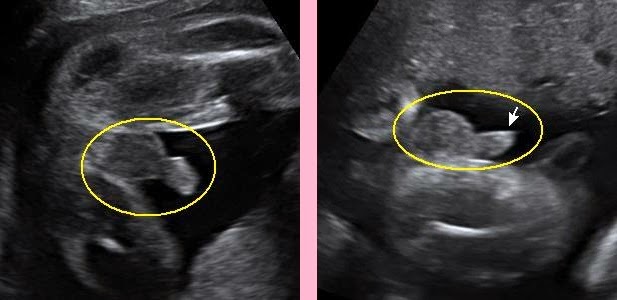

Особенности УЗИ при определении пола ребенка

Раздел: Идеи и советы